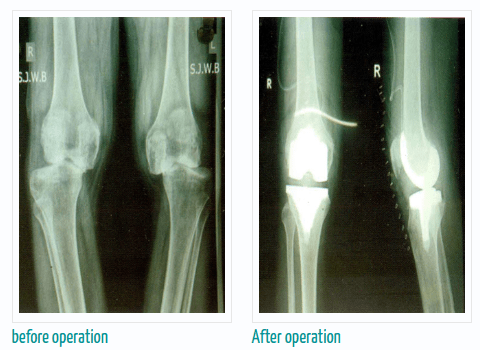

If you are thinking about getting arthroscopic surgery, consider seeing Dr. Murtaza Adeeb. He is a great doctor for joint replacement, and you can meet him at the Advanced Bone Care Clinic wanawadi Road Fatimanagar Pune.

Dr. Murtaza Adeeb is known for being really good at robotic knee, hip, and joint replacement surgery. To make an appointment with Dr. Murtaza Adeeb,